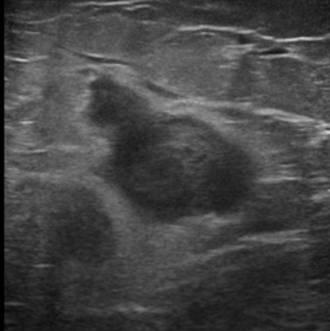

Di căn vú

» Thông tin: Nữ giới – 70 tuổi.

» Lâm sàng: Khối tuyến vú / K hắc tố.